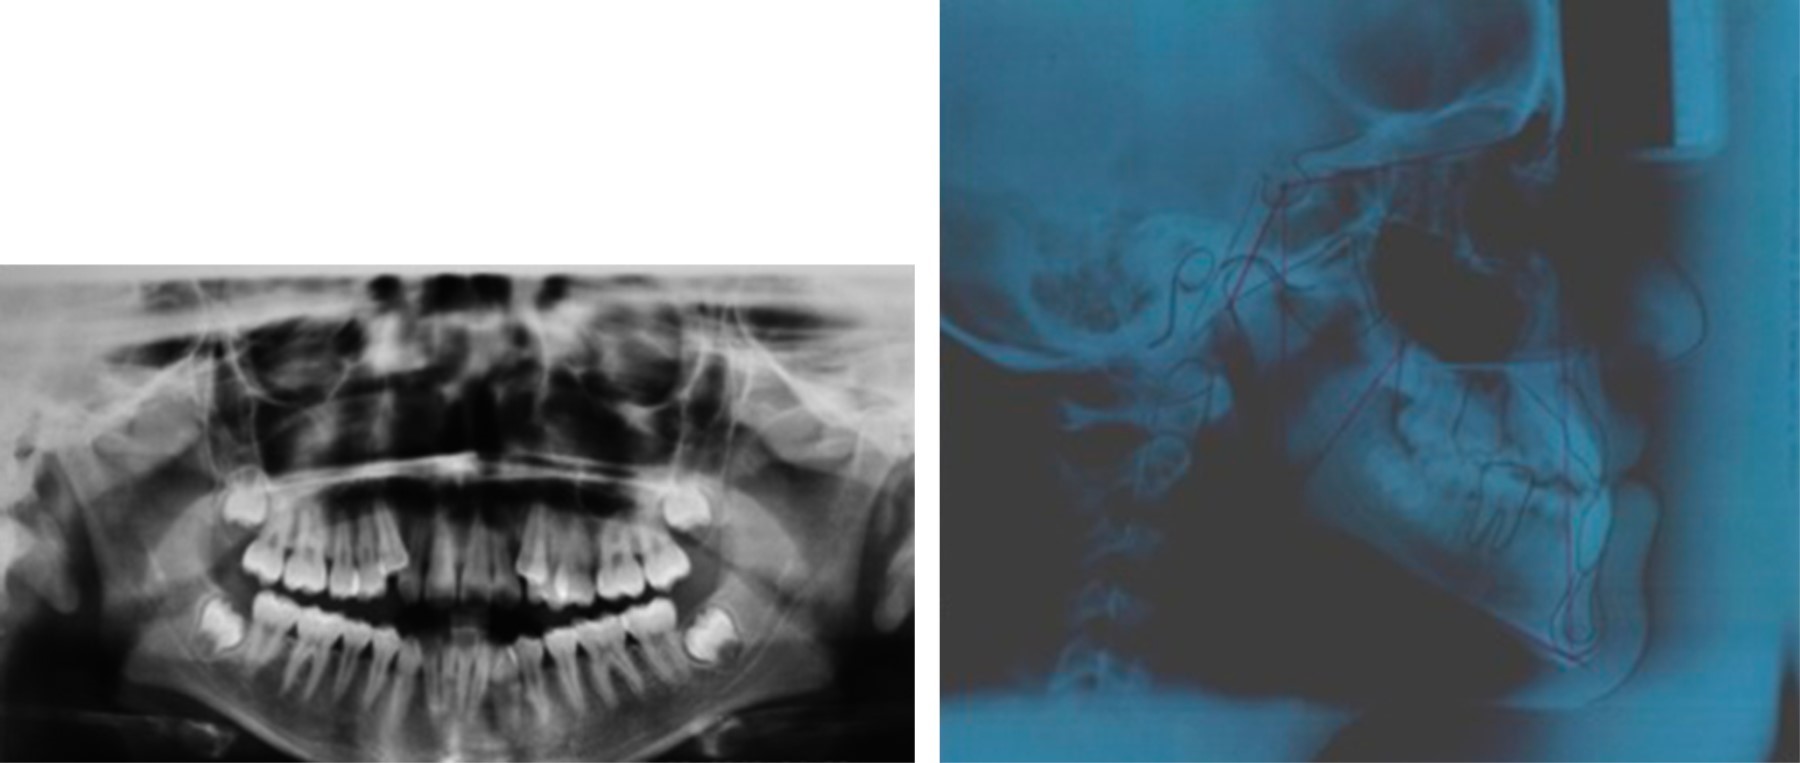

Panoramic X-ray: we observed pneumatized maxillary sinuses, asymmetric mandibular body and branches, retention of upper and lower third molars, and ectopic upper canines (Figure 2).

Lateral skull X-ray: class III bone, the open goniac angle is observed and in the ANB the dental compensations characteristic of a dental class III such as proinclined upper incisors and retroinclination of the lower incisors, via a permeable area, mandibular prognathism, and lower lip protrusion (Figure 2).